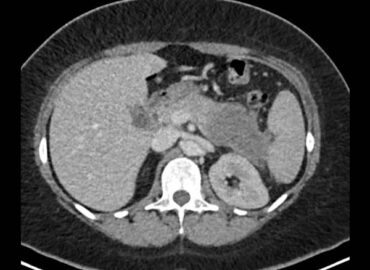

Pte femenino de 52 años, Mc: dolor abdominal difuso, App: hta, Mh: Losartan, A qx: osteosíntesis lumbar.